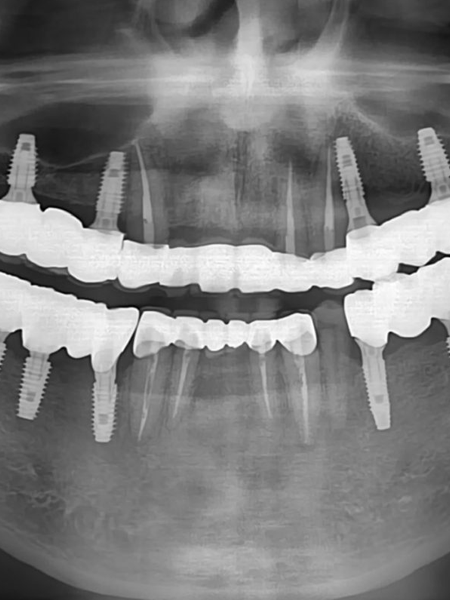

치아 아래 숨어 있는 뼈, 신경, 구조까지 정확히 파악하고 치료합니다. 특히 임플란트, 발치, 턱관절처럼 위험 요소가 있는 시술일수록 전문의의 구조 이해와 설계력이 치료 결과를 좌우합니다.

결과로 말합니다.

시술 전과 후, 직접 확인해보세요.

굿플러스치과 전후사진은 환자분의 동의하에 동일한 조건에서 촬영되었으며, 어떠한 보정도 하지 않았습니다.

모든 시술은 환자분의 상태에 따라 부작용이 발생할 수 있음을 의료법에 따라 고지합니다.